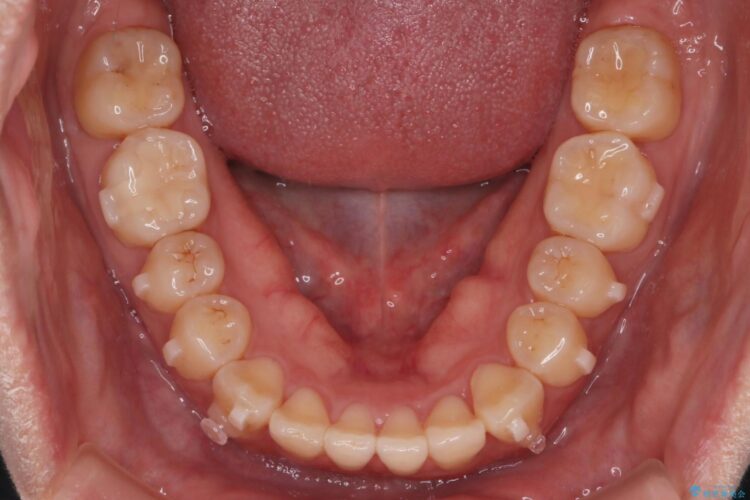

上の前歯のねじれが気になるとご来院された患者様です。

前歯の捻れとがたつきを改善するために、IPR(歯と歯の間を削る処置)と歯列拡大をすることで歯並びを整えていく治療計画を立てました。